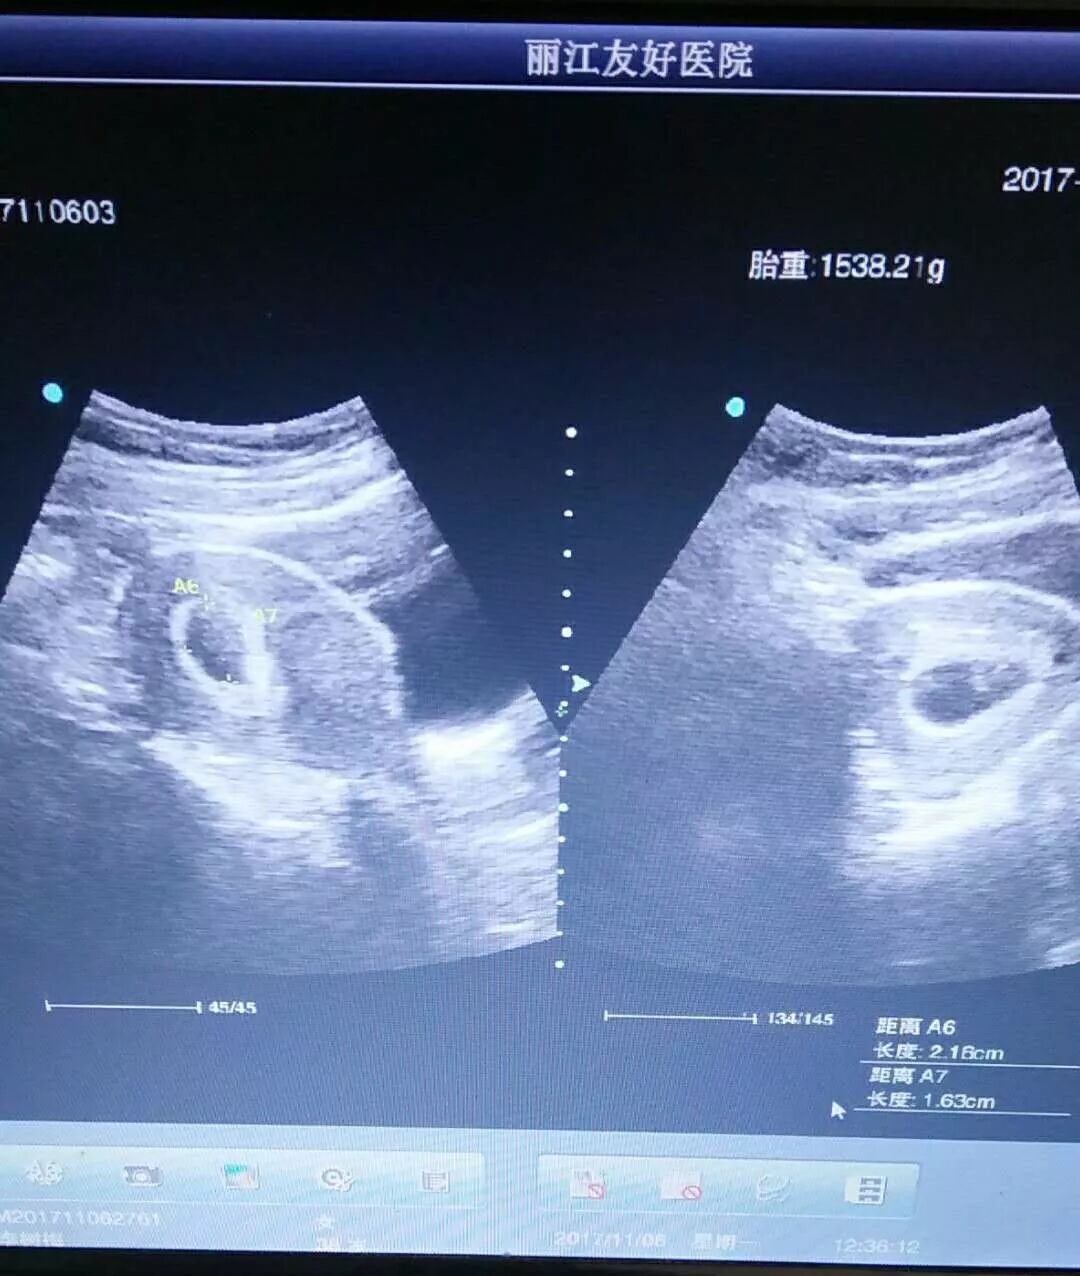

本次怀孕经历波折

孕酮低,出血,经过保胎,终于渡过难关

看到双胞胎的孩子发育正常

好激动,很开心,苦尽甘来了